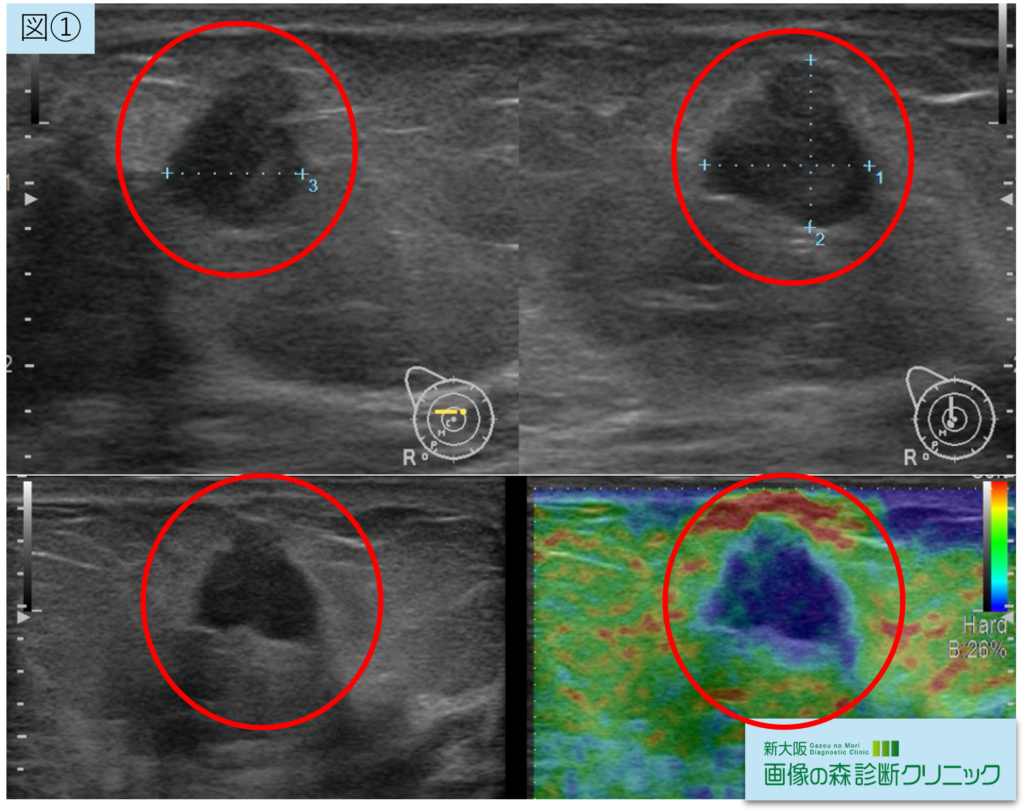

症例画像から図①:エコー画像、図②:MRI画像(赤〇が腫瘍部位です)

エコーでは右乳癌を疑い、造影MRI検査を行うことになりました。